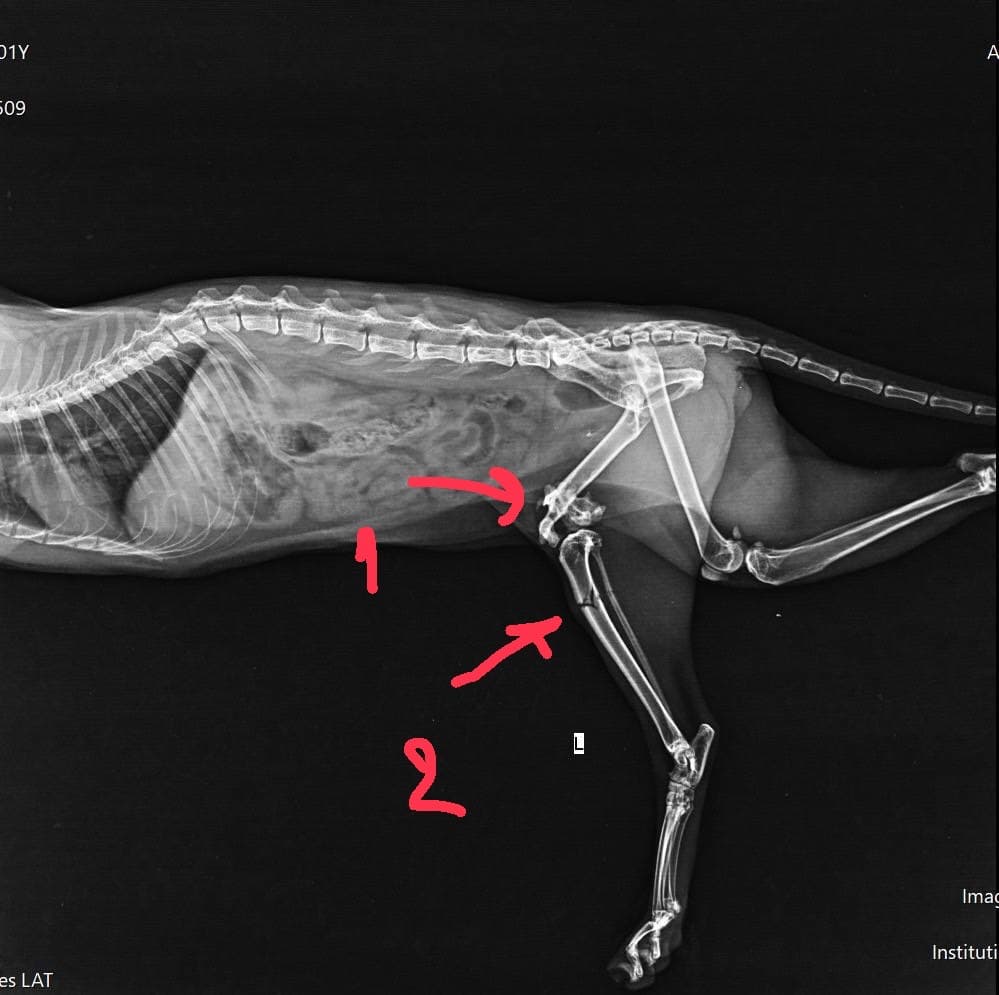

📌หาบ้านให้น้องแมว📌 น้องชื่อ สามสี เป็นแมวสู้ชีวิตมาก เรื่องราวคร่าวๆดูจากภาพแรกได้เลยนะคะ น้องเสียตาไปข้างนึง โดนรถทับหลายรอบแล้ว ตอนนี้รักษาจนหายแล้ว แต่น้องเดินกระเพกนิดนึง แต่ความซนเต็ม 100 ค่ะ ขอบ้านที่อบอุ่นให้เค้าด้วยนะคะ พิกัด : หมู่บ้านโนเบิลคิวบ์ พัฒนาการ สวนหลวง